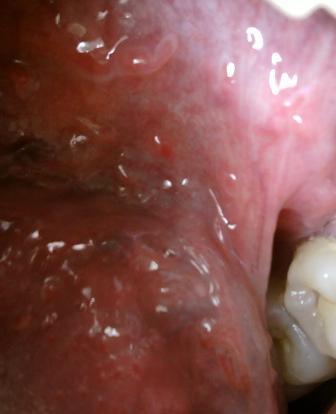

石家庄九州皮肤病医院 > 尖锐湿疣 > > > 尖锐湿疣隐形感染应该怎么治疗尖锐湿疣是生活中很常见的一种皮肤性病,患病之后,大家应该谨慎对待,及时去专业正规的医院接受治疗是很关键的,任何击毙个早期都是治疗疾病的关键时期你,大家患病之后不要拖延治疗,这样只会导致病情越来越严重,不利于疾病今后的治疗和康复。

尖锐湿疣隐形感染应该怎么治疗尖锐湿疣性病在治疗上是有一定的难度的,但是并不是不治之症,所以在这里专家温馨提示:只要对症治疗,疾病是可以早日康复的。尖锐湿疣皮肤性病不及时治疗危害很大,危害人们身体健康,诱发炎症,还会致癌。尖锐湿疣病毒传染性很强,为了避免尖锐湿疣对他人造成危害,所以患病之后及时去专业的医院接诊很关键。尖锐湿疣是一种比较顽固的疾病,在治疗上是有一定的难度的,所以建议大家在治疗的时候不应该盲目,而是应该及时选择一家比较专业的医院。